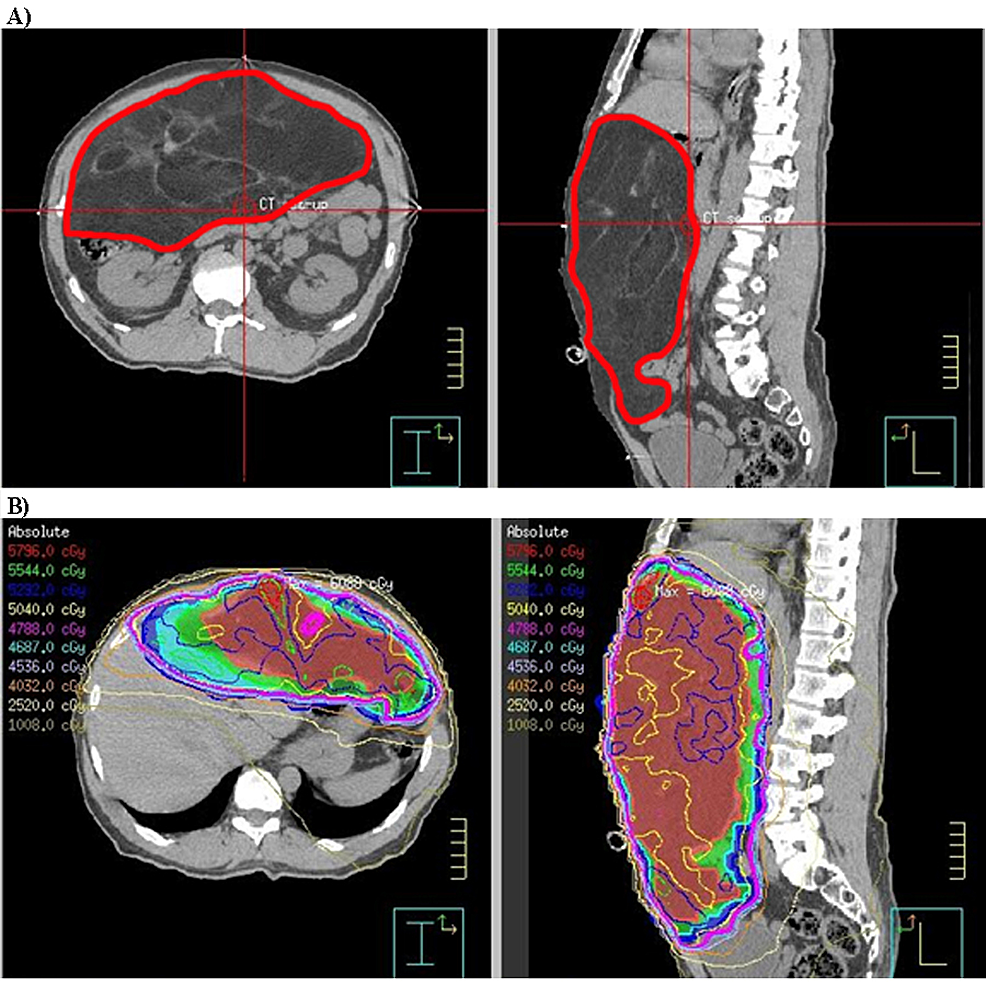

Cureus | Long-Term Quality Of Life Of Retroperitoneal Sarcoma Patients

www.cureus.com

www.cureus.com

sarcoma retroperitoneal radiotherapy figure scan ct patient plan term treated patients operative surgery pre quality long life cureus intensity modulated